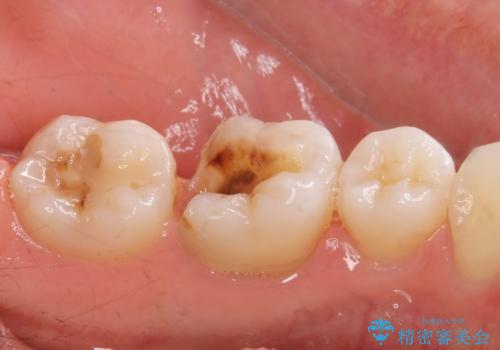

- メタルインレーが取れてしまって来院。

虫歯が再発していたので拡大鏡下で取り切った後、e-maxインレーにて治療しました。

また、一番奥の歯も古い樹脂の治療がされていたため虫歯の予防のために樹脂を取り除き、う蝕がないことを確認してe-maxインレーで治療しました。

樹脂(プラスチック)の治療は白くて審美性は良いが経年的に劣化します。

た歯質との隙間ができてしまうため虫歯の再発のリスクが高いです。

e-max(セラミック)は歯質との隙間が出来にくく虫歯の再発のリスクが低くなります。